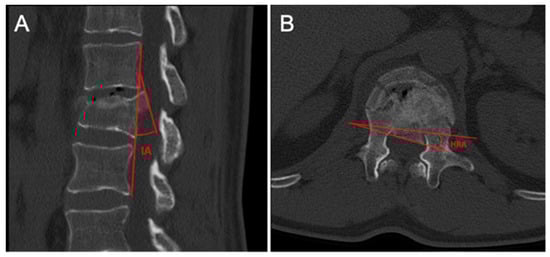

- Inversion angle (IA): measured on the sagittal plane at the point of maximum protrusion of the fragment, it is defined as the intersection angle between the tangent line to the “ideal” posterior vertebral wall and the line to the posterior margin of the bone fragment.

- Horizontal rotation angle (HRA): measured on the axial plane at the point of maximum stenosis, it is defined as the intersection angle between the line tangent to the posterior “ideal” vertebral wall and the line to the posterior margin of the intracanalar fragment.